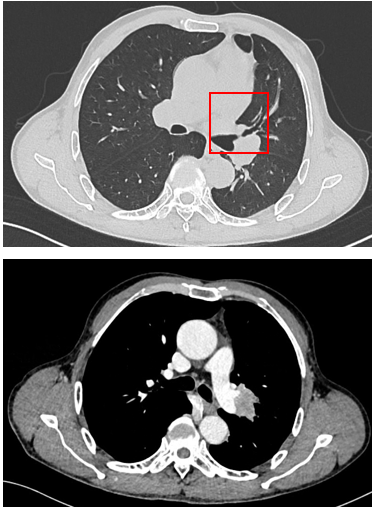

胸部CT显示左侧上叶支气管旁部发现一不规则、边界不清的软组织肿块,大小约为41mm×26mm。增强扫描后,肿瘤呈显著不均匀强化,与肿大的淋巴结粘连且难以区分,部分包裹左上叶支气管,导致管腔狭窄。左上叶肺叶间裂增厚,多个结节灶提示可能存在肺内转移。

治疗缓解评估:影像学(CT)显示原发肿瘤及叶间淋巴结明显缩小;支气管镜显示左上叶开口通畅,原肿块显著退缩,可见白色坏死组织;疗效评估为PR。

手术治疗:新辅助治疗完成后6周,行VATS辅助左上肺叶切除+肺门及纵隔淋巴结清扫;术中血管解剖清晰,淋巴结清扫顺利;切口小,胸腔镜辅助下完成重建。